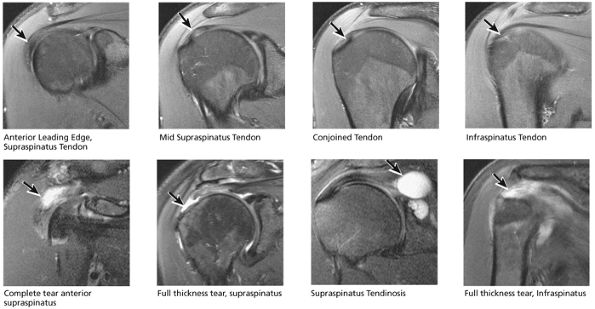

FIGURE 8.32 Rotator Cuff.